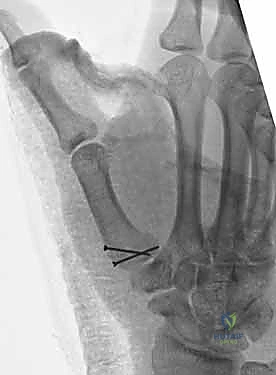

1. الرد المغلق والتثبيت عبر الجلد بالإبر (CRPP - Closed Reduction and Percutaneous Pinning)

هذا الإجراء هو الخيار المفضل لكسور "بينيت" التي يمكن إعادتها لمكانها بدون فتح جراحي كبير.

* الخطوات: يتم إجراء العملية تحت التخدير الموضعي أو الكلي. باستخدام جهاز الأشعة السينية المباشر في غرفة العمليات (C-arm Fluoroscopy)، يقوم البروفيسور هطيف برد الكسر إلى مكانه المثالي.

* بعد ذلك، يتم إدخال إبر معدنية دقيقة (K-wires أو Kirschner wires) عبر الجلد مباشرة لتثبيت قاعدة المشط الأول بالعظم المربعي، وأحياناً بالمشط الثاني لزيادة الاستقرار.

* الميزة: شقوق صغيرة جداً، ألم أقل، وشفاء أسرع. يتم إزالة هذه الإبر عادة في العيادة بعد 4 إلى 6 أسابيع.